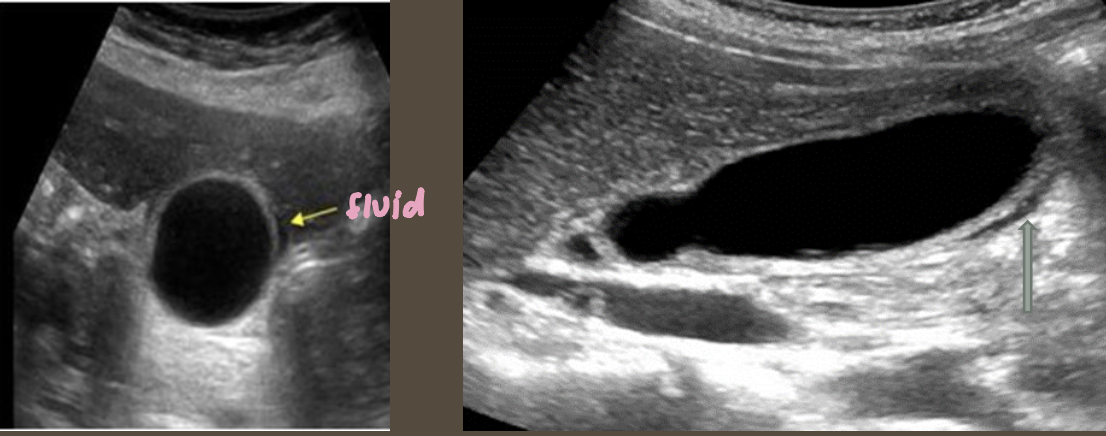

Simple Renal Cyst → common lesion of kidney, fluid-filled sac (benign, Bozniak 1)

2D US: anechoic, well-defined smooth, thin wall, round or ovoid, posterior enhancement

color doppler: avascular

Hydronephrosis → dilation of renal collecting system from mechanical obstruction or functional dysfunction (calculi, mass, trauma, pregnancy)

2D US: grade 1 (mild) → pelviectasis, cortex preserved, grade 2 (mild to moderate) → expands into major calyces, cortex preserved, grade 3 (moderate) → expand all calyces, entire pelvis dilated, cortex preserved, grade 4 (severe) → cortical thinning, AKI to CKD, creatinine >1.2

DDX: parapelvic cysts